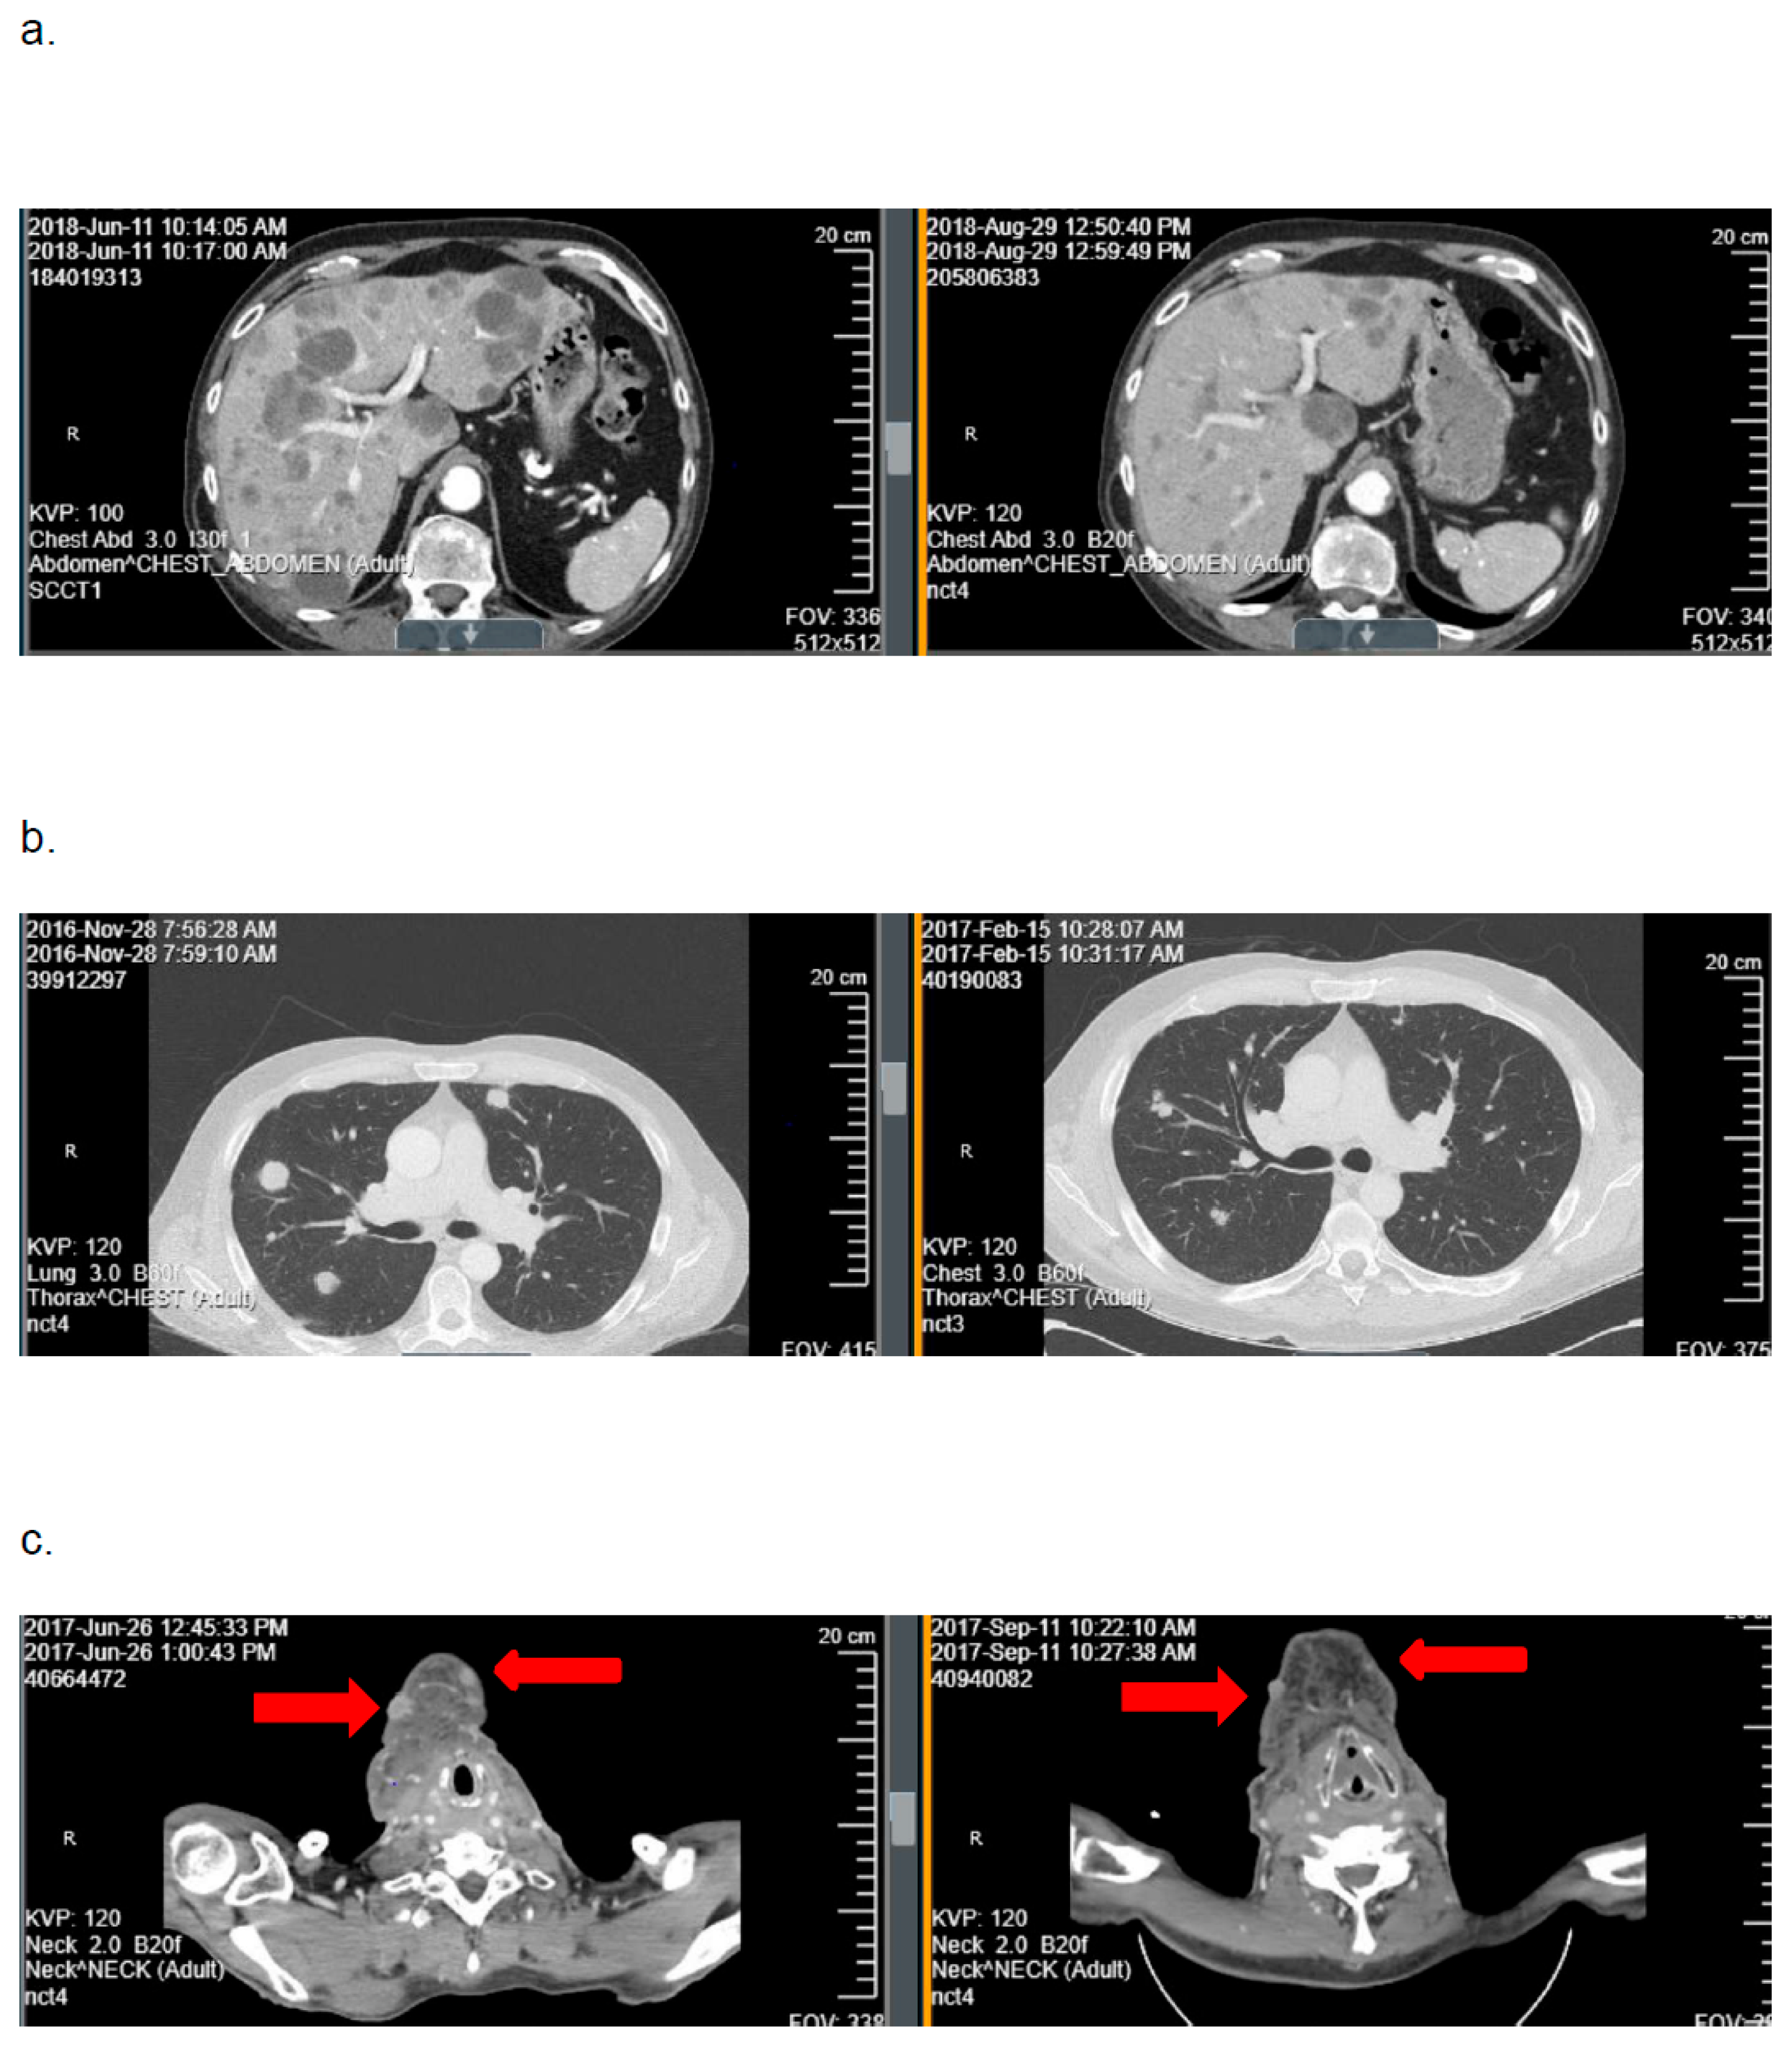

3.3. Objective Response Rate

3.4. TP53 Mutational Status and Tumor Response